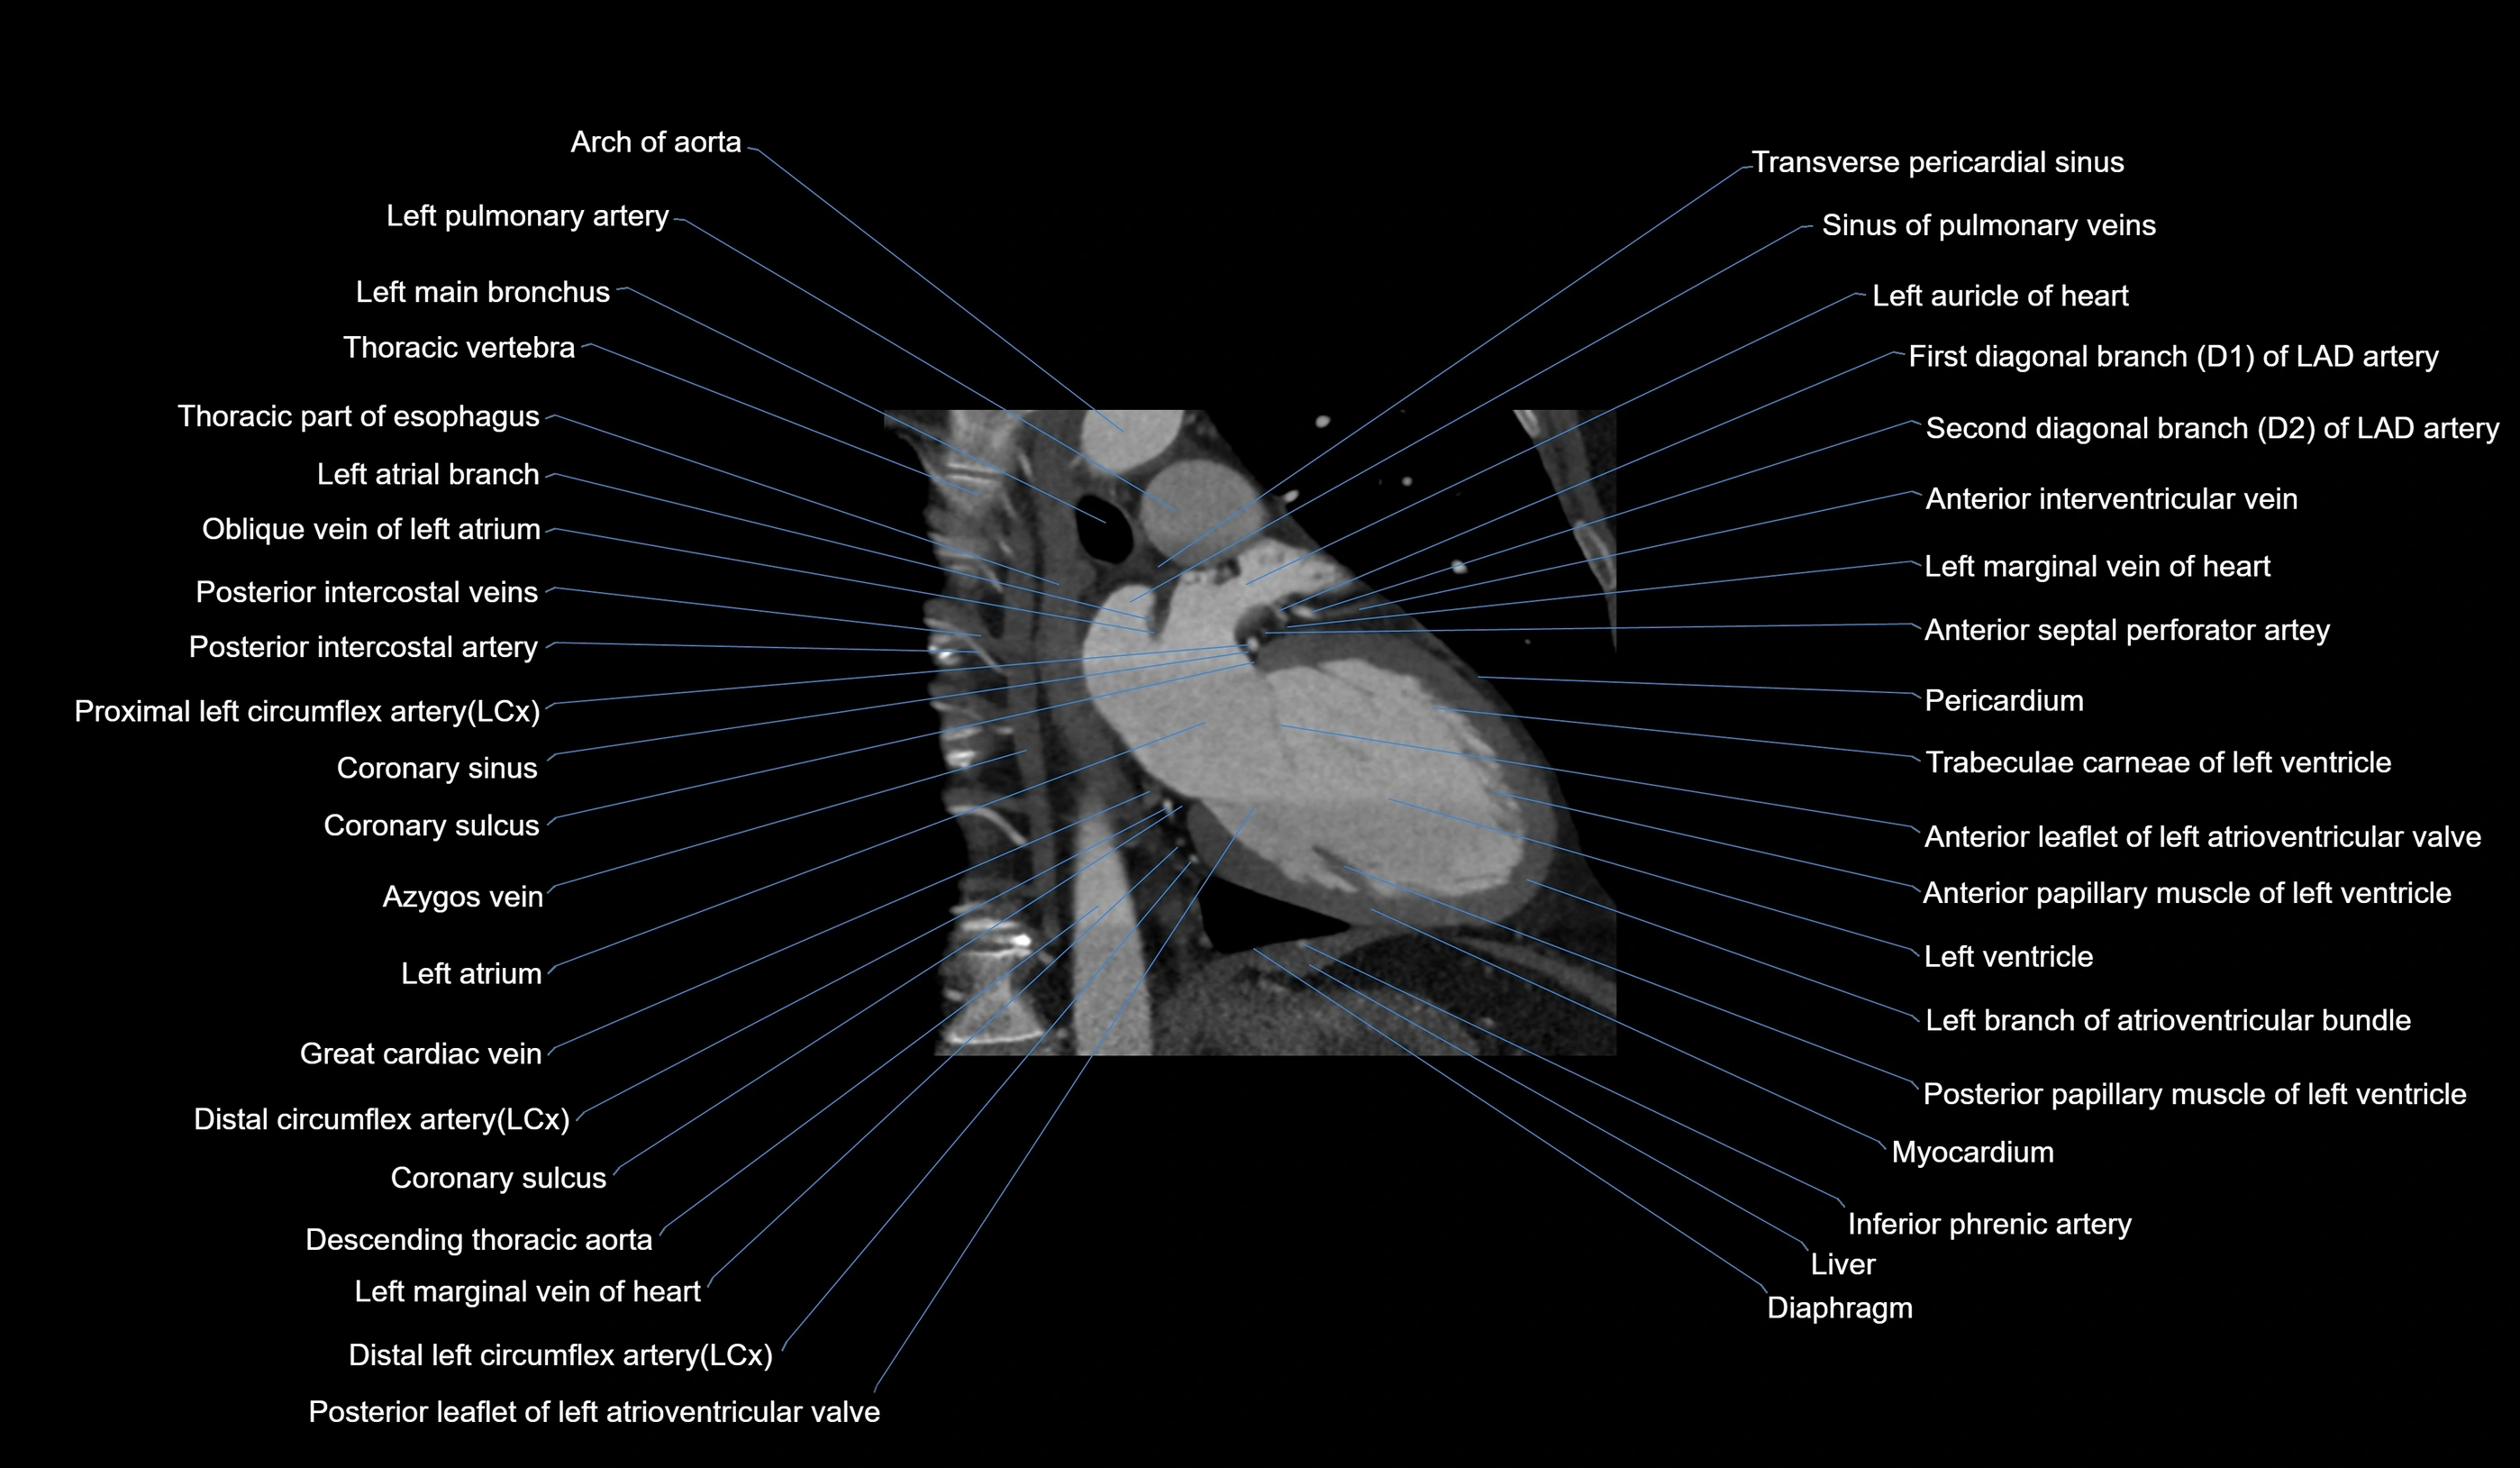

CT Appearance

Non-contrast CT (Calcium Scoring):

-

AM artery visualized for coronary calcium scoring

Calcified plaques appear as hyperdense foci; scored with Agatston method

CT Coronary Angiography (CCTA):

Best non-invasive modality for acute marginal artery visualization

Shows origin, course along the acute margin, and right ventricular branches

Detects stenosis, occlusion, calcified and non-calcified plaques, aneurysm, or anomalous course

Multiplanar reformats and 3D reconstructions help in pre-PCI and surgical planning

Critical for assessing right ventricular infarction risk in RCA disease

MRI image

CT images